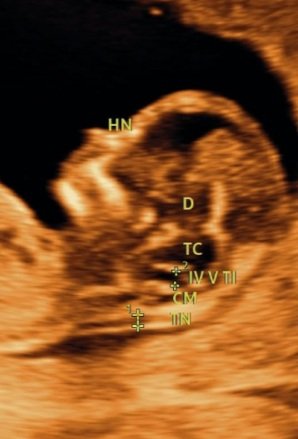

La unidad de diagnóstico prenatal de Centro Procrea se encarga de la realización de ecografías obstétrico-ginecológicas de alta resolución, así como del diagnóstico y coordinación del manejo de la patología fetal. Para ello contamos con ecógrafos de última generación con posibilidad de estudio doppler y tridimensional para un estudio detallado.

Este ultrasonido se recomienda para poder detectar ciertas anomalías en el feto y la formación del mismo, que pueden resultar en síndrome de down por ejemplo; ya que en este periodo el feto debe de contar con ciertas características y mediciones especificas. Aunque la mayoría de los bebés nacen sanos, aproximadamente del tres al cinco por ciento de todos los bebés nacen con trastornos genéticos o síndromes. Este tipo de ultrasonido debe realizarse en una clínica o centro especializado en ultrasonidos prenatales, como Centro Procrea. En este ultrasonido se debe observar:

✅𝐓𝐫𝐚𝐬𝐥𝐮𝐜𝐞𝐧𝐜𝐢𝐚 𝐧𝐮𝐜𝐚𝐥 – Es un examen que mide el engrosamiento del pliegue de la nuca. Esta es un área de tejido en la parte posterior del cuello de un feto. Ayuda a evaluar el riesgo para síndrome de Down y otros problemas genéticos en el bebé.

✅𝐃𝐮𝐜𝐭𝐮𝐬 𝐯𝐞𝐧𝐨𝐬𝐨 –El ductus venoso permite el paso directo de sangre oxigenada desde la vena umbilical a la circulación coronaria y cerebral, el flujo ausente o reverso durante la contracción atrial es un marcador de aneuploidías y/o cardiopatías.